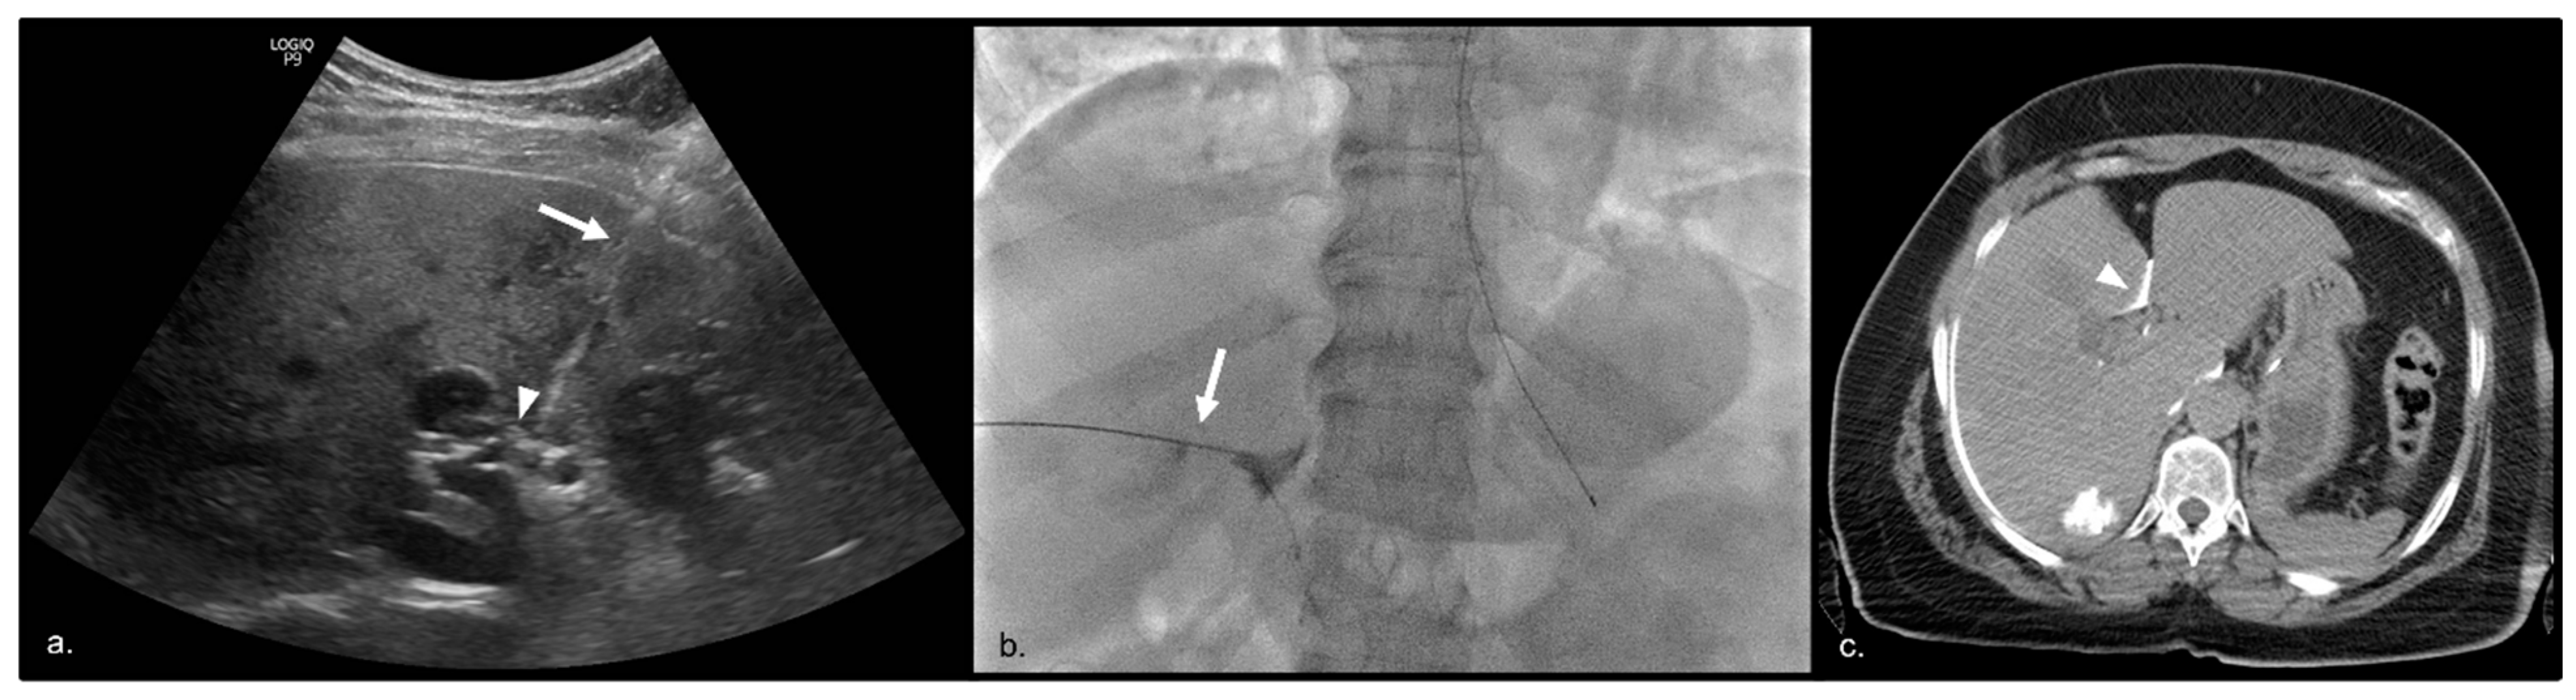

- He, K.S.; Fernando, R.; Cabrera, T.; Valenti, D.; Algharras, A.; Martínez, N.; Liu, D.M.; Noel, G.; Muchantef, K.; Bessissow, A.; et al. Hepatic Hilar Nerve Block for Hepatic Interventions: Anatomy, Technique, and Initial Clinical Experience in Thermal Ablation of Liver Tumors. Radiology 2021, 301, 223–228. [Google Scholar] [CrossRef] [PubMed]

- Parhar, D.; Baum, R.A.; Spouge, R.; Yan, T.; Ho, S.; Hadjivassiliou, A.; Machan, L.; Legiehn, G.; Klass, D.; Dhatt, R.; et al. Hepatic Hilar Nerve Block for Adjunctive Analgesia during Percutaneous Thermal Ablation of Hepatic Tumors: A Retrospective Analysis. J. Vasc. Interv. Radiol. 2023, 34, 370–377. [Google Scholar] [CrossRef] [PubMed]